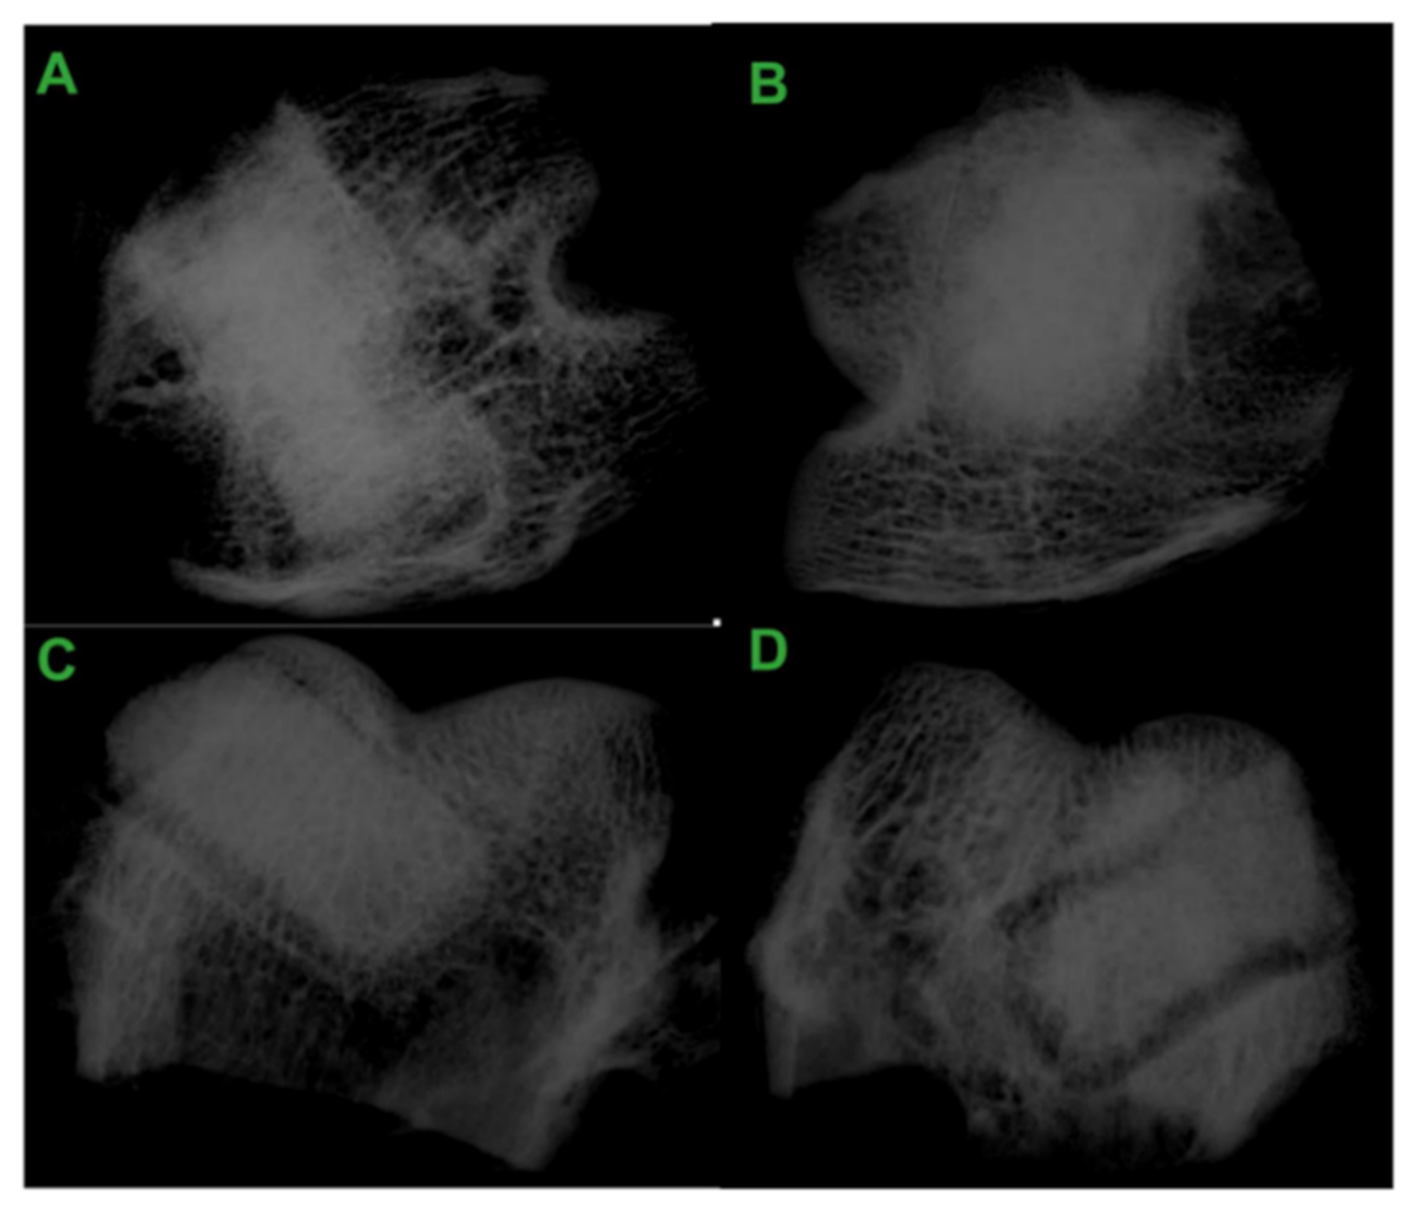

- Kommareddy, K.P.; Lange, C.; Rumpler, M.; Dunlop, J.W.C.; Manjubala, I.; Cui, J.; Kratz, K.; Lendlein, A.; Fratzl, P. Two stages in three-dimensional in vitro growth of tissue generated by osteoblastlike cells. Biointerphases 2010, 5, 45–52. [Google Scholar] [CrossRef] [PubMed]